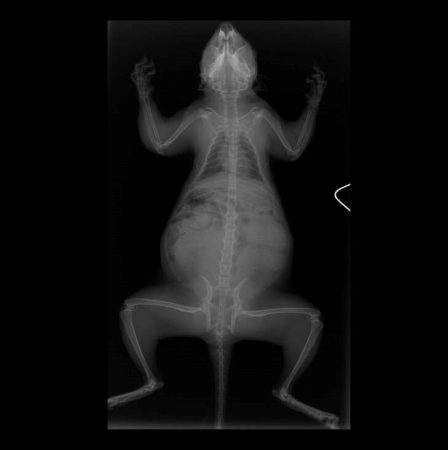

What do you see in this x-ray?

Did you notice that this squirrel is pregnant?! If you look closely at the x-rays, you can see the spines and skulls of her developing fetuses!